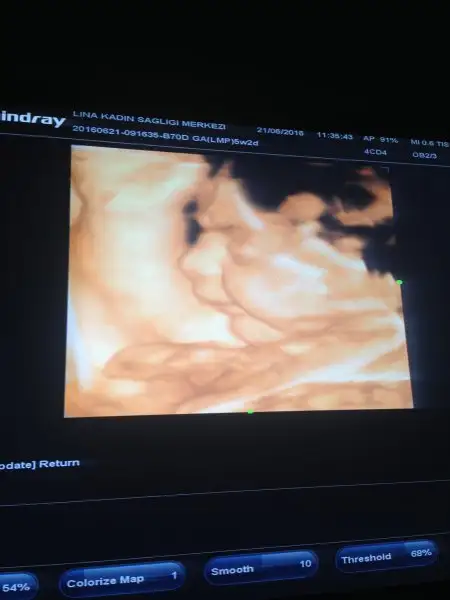

Maşallah diyelim teyzeleri :) bizim kızımızda biraz Tonbiş doktorum dana diye seviyor 31 haftalikken 2 kg idi 42 cm boyu da. Şekerden şüphelendiler ama sukur onunla ilgili değilmiş sanirim benim fazla meyve yememden oluyor. Böbreğinde de sağda buyume var Dedi bakalım bir daha kı gidişimize insallah azalma olmustur. O resimde de bacağını emiyordu yavrum :) Rabbim hepimizin hayirlisiyla kucağına almayı nasip etsin